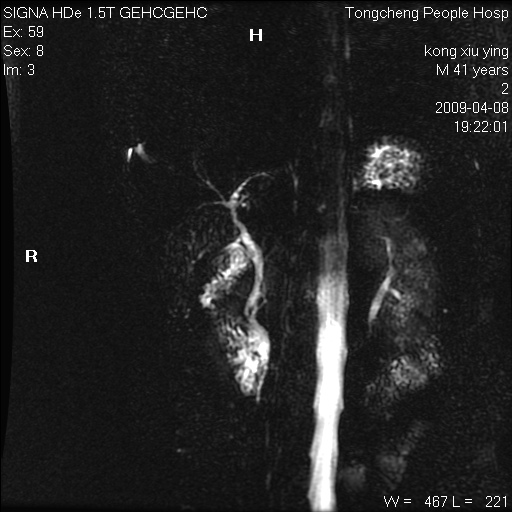

标题: CL1008:【经典】胆囊石榴籽样结石。

女,41岁。健康体检——彩超提示:胆囊显示不清。平素健康,无不适感。

腹部mr扫描及mrcp,图像如下: